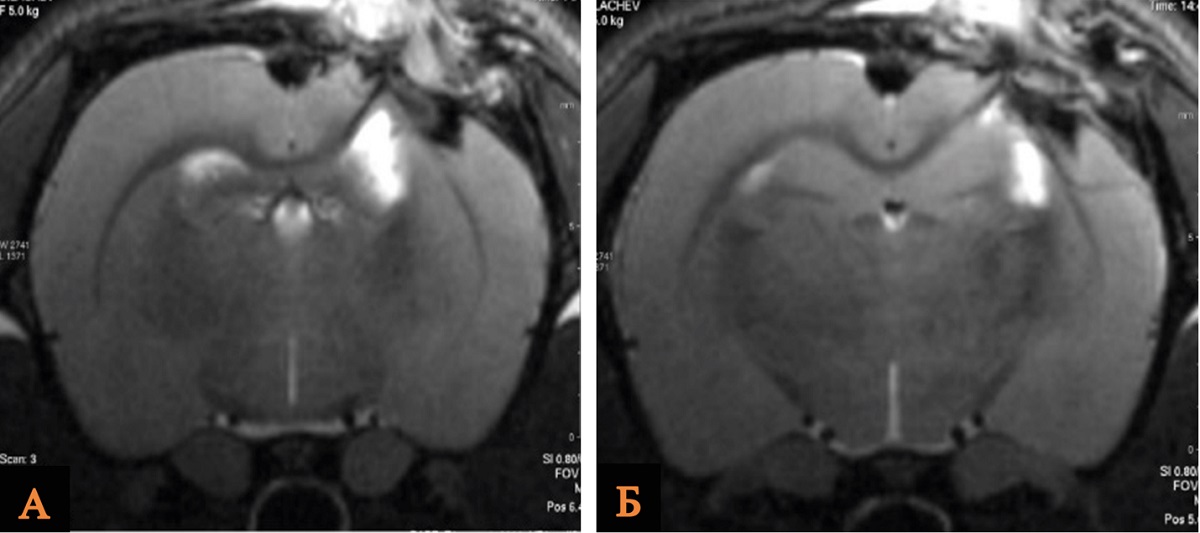

При изучении объема повреждения головного мозга крыс после ОЧМТ при введении хлорида лития в дозе 21 мг/кг через 60 мин проведено исследование объема повреждения головного мозга по данным морфометрического анализа МР-изображений в группах ложнооперированных животных (n = 10), группе Контроль (n = 10) и ОЧМТ+Литий 60 мин/21 мг (n = 10).

При анализе данных МРТ выявлено, что средний объем повреждения головного мозга крыс был статистически значимо меньше в группе ОЧМТ+Литий 60 мин/21 мг, чем в группе Контроль. По данным МРТ, исследуемый показатель в группах сравнения составил 25,5 mm3 и 35,0 mm3 соответственно (рис. 2, табл. 2).

Рис. 2. МРТ зоны ушиба головного мозга крысы после введения хлорида лития в дозе 21 мг/кг через 60 мин в сравнении с контрольной группой

Примечание: А – группа Контроль; Б – группа ОЧМТ+Литий 60 мин/21 мг. Изображение авторов, получено в ходе оригинального исследования.

Таблица 2

Объем повреждения головного мозга крыс в группе ОЧМТ+Литий 60 мин/21 мг и группах сравнения по данным МРТ-изображений на 14-е сутки наблюдения

Группа | Объем повреждения головного мозга мм 3 | p, значимость относительно ложнооперированных животных | p, значимость относительно контрольных животных |

Ложнооперированные животные | 12,0 [8,0–14,5] | – | – |

Контроль (n = 10) | 35,0 [30–36] | 0,0001 | – |

ОЧМТ+Литий 60 мин/21 мг (n = 10) | 25,5 [21–29,5] | 0,01 | 0,03 |

Примечание: составлено авторами.